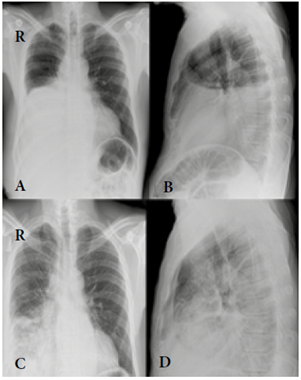

El caso corresponde a un hombre de 56 años de edad, residente en Ibagué (Tolima, Colombia), de profesión mecánico automotor/industrial, a quien en enero de 2014 se le hallaron tres masas en región torácica con diagnóstico inicial de lipomas, y a quien se remitió a cirugía con el fin de retirárselos. Se le solicitaron exámenes preoperatorios, entre estos una radiografía de tórax (figura 1). Los lipomas fueron extraídos por cirugía ambulatoria y se tomaron muestras de tejido muscular de las regiones torácica y pleural que se remitieron a estudio histopatológico en la ciudad de Bogotá.

Figura 1 Radiografía de tórax: en la proyección posterior anterior se evidencia opacidad en el tercio interior del hemitórax izquierdo con borramiento del hemidiafragma con ascenso pulmonar ipsilateral (A). En la proyección lateral (B) se visuali za opacidad en 2/3 del hemitórax. En (C) se observa aumento de la silueta pulmonar y del diámetro pulmonar con presen cia de nódulos y posible afectación de los tejidos adyacentes. (D) Hay expansión pulmonar con presencia de consolidación aparentemente paraneumónica